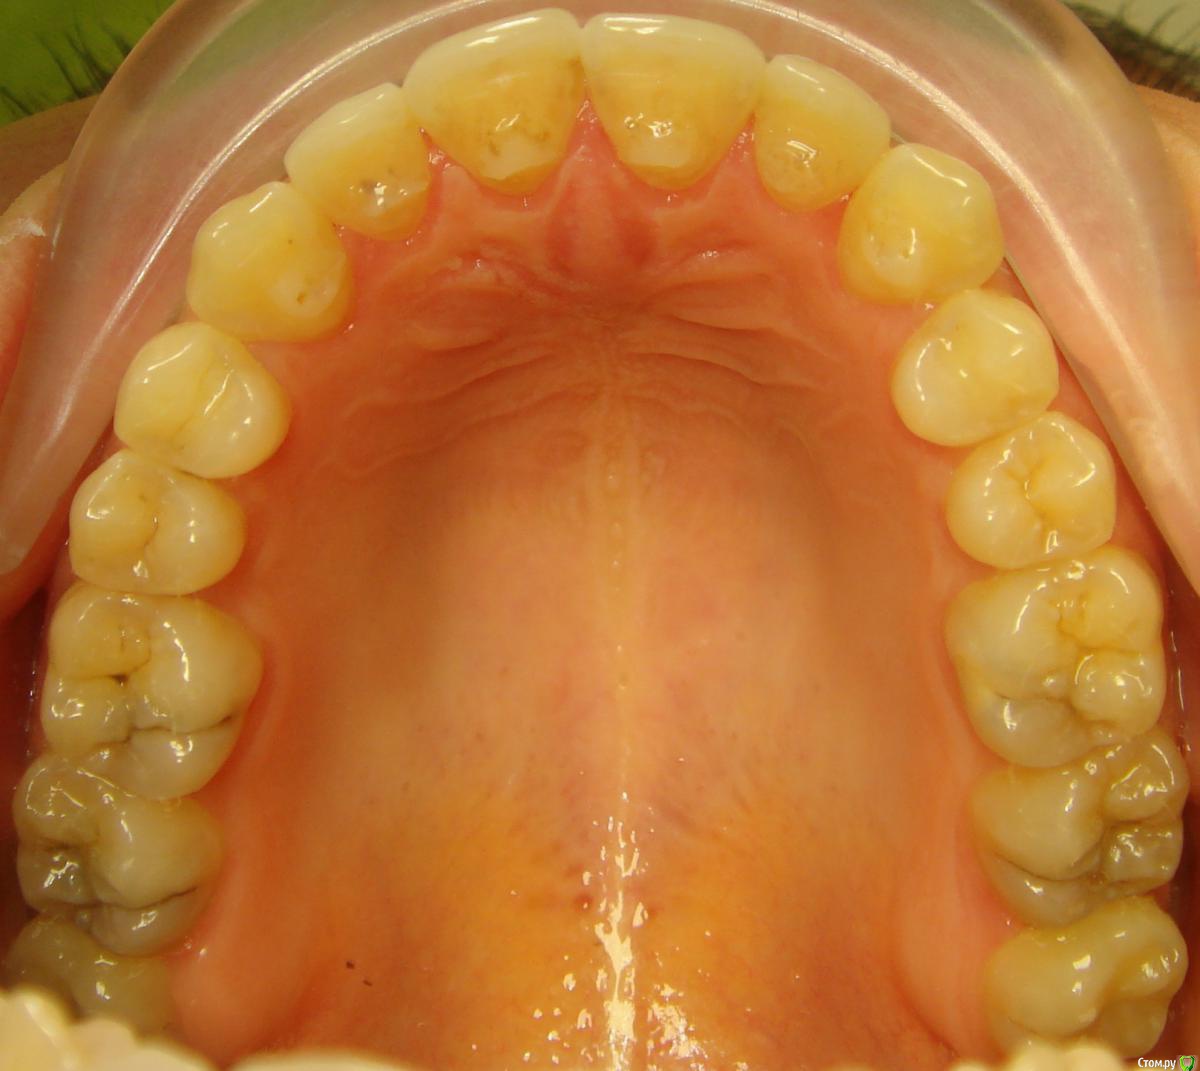

Opdihatop Опубликовано 4 марта, 2017 Поделиться Опубликовано 4 марта, 2017 И снова здравствуйте, коллеги. Вот такой вот случай к рассмотрению. Много лет назад пациентка уже проходила "камуфляжное" лечение. Со слов пациентки оно было закончено с передним открытым прикусом. Сейчас ситуация такая. Пациентка думает над ортохирургией, но меня смущает фронт н/ч. И по снимкам и по ситуации во рту корни 32, 31, 42, 43 зубов фенестрировали лингвальную кортикалку почти на всем протяжении, 33 - вестибулярную. Вопрос вот в чем: что делатьс этими зубами? Возможно ли их поставить на место? Или лучше не трогать, дольше простоят? Ссылка на комментарий

Opdihatop Опубликовано 26 марта, 2017 Автор Поделиться Опубликовано 26 марта, 2017 Прошу:313233414243 Ссылка на комментарий